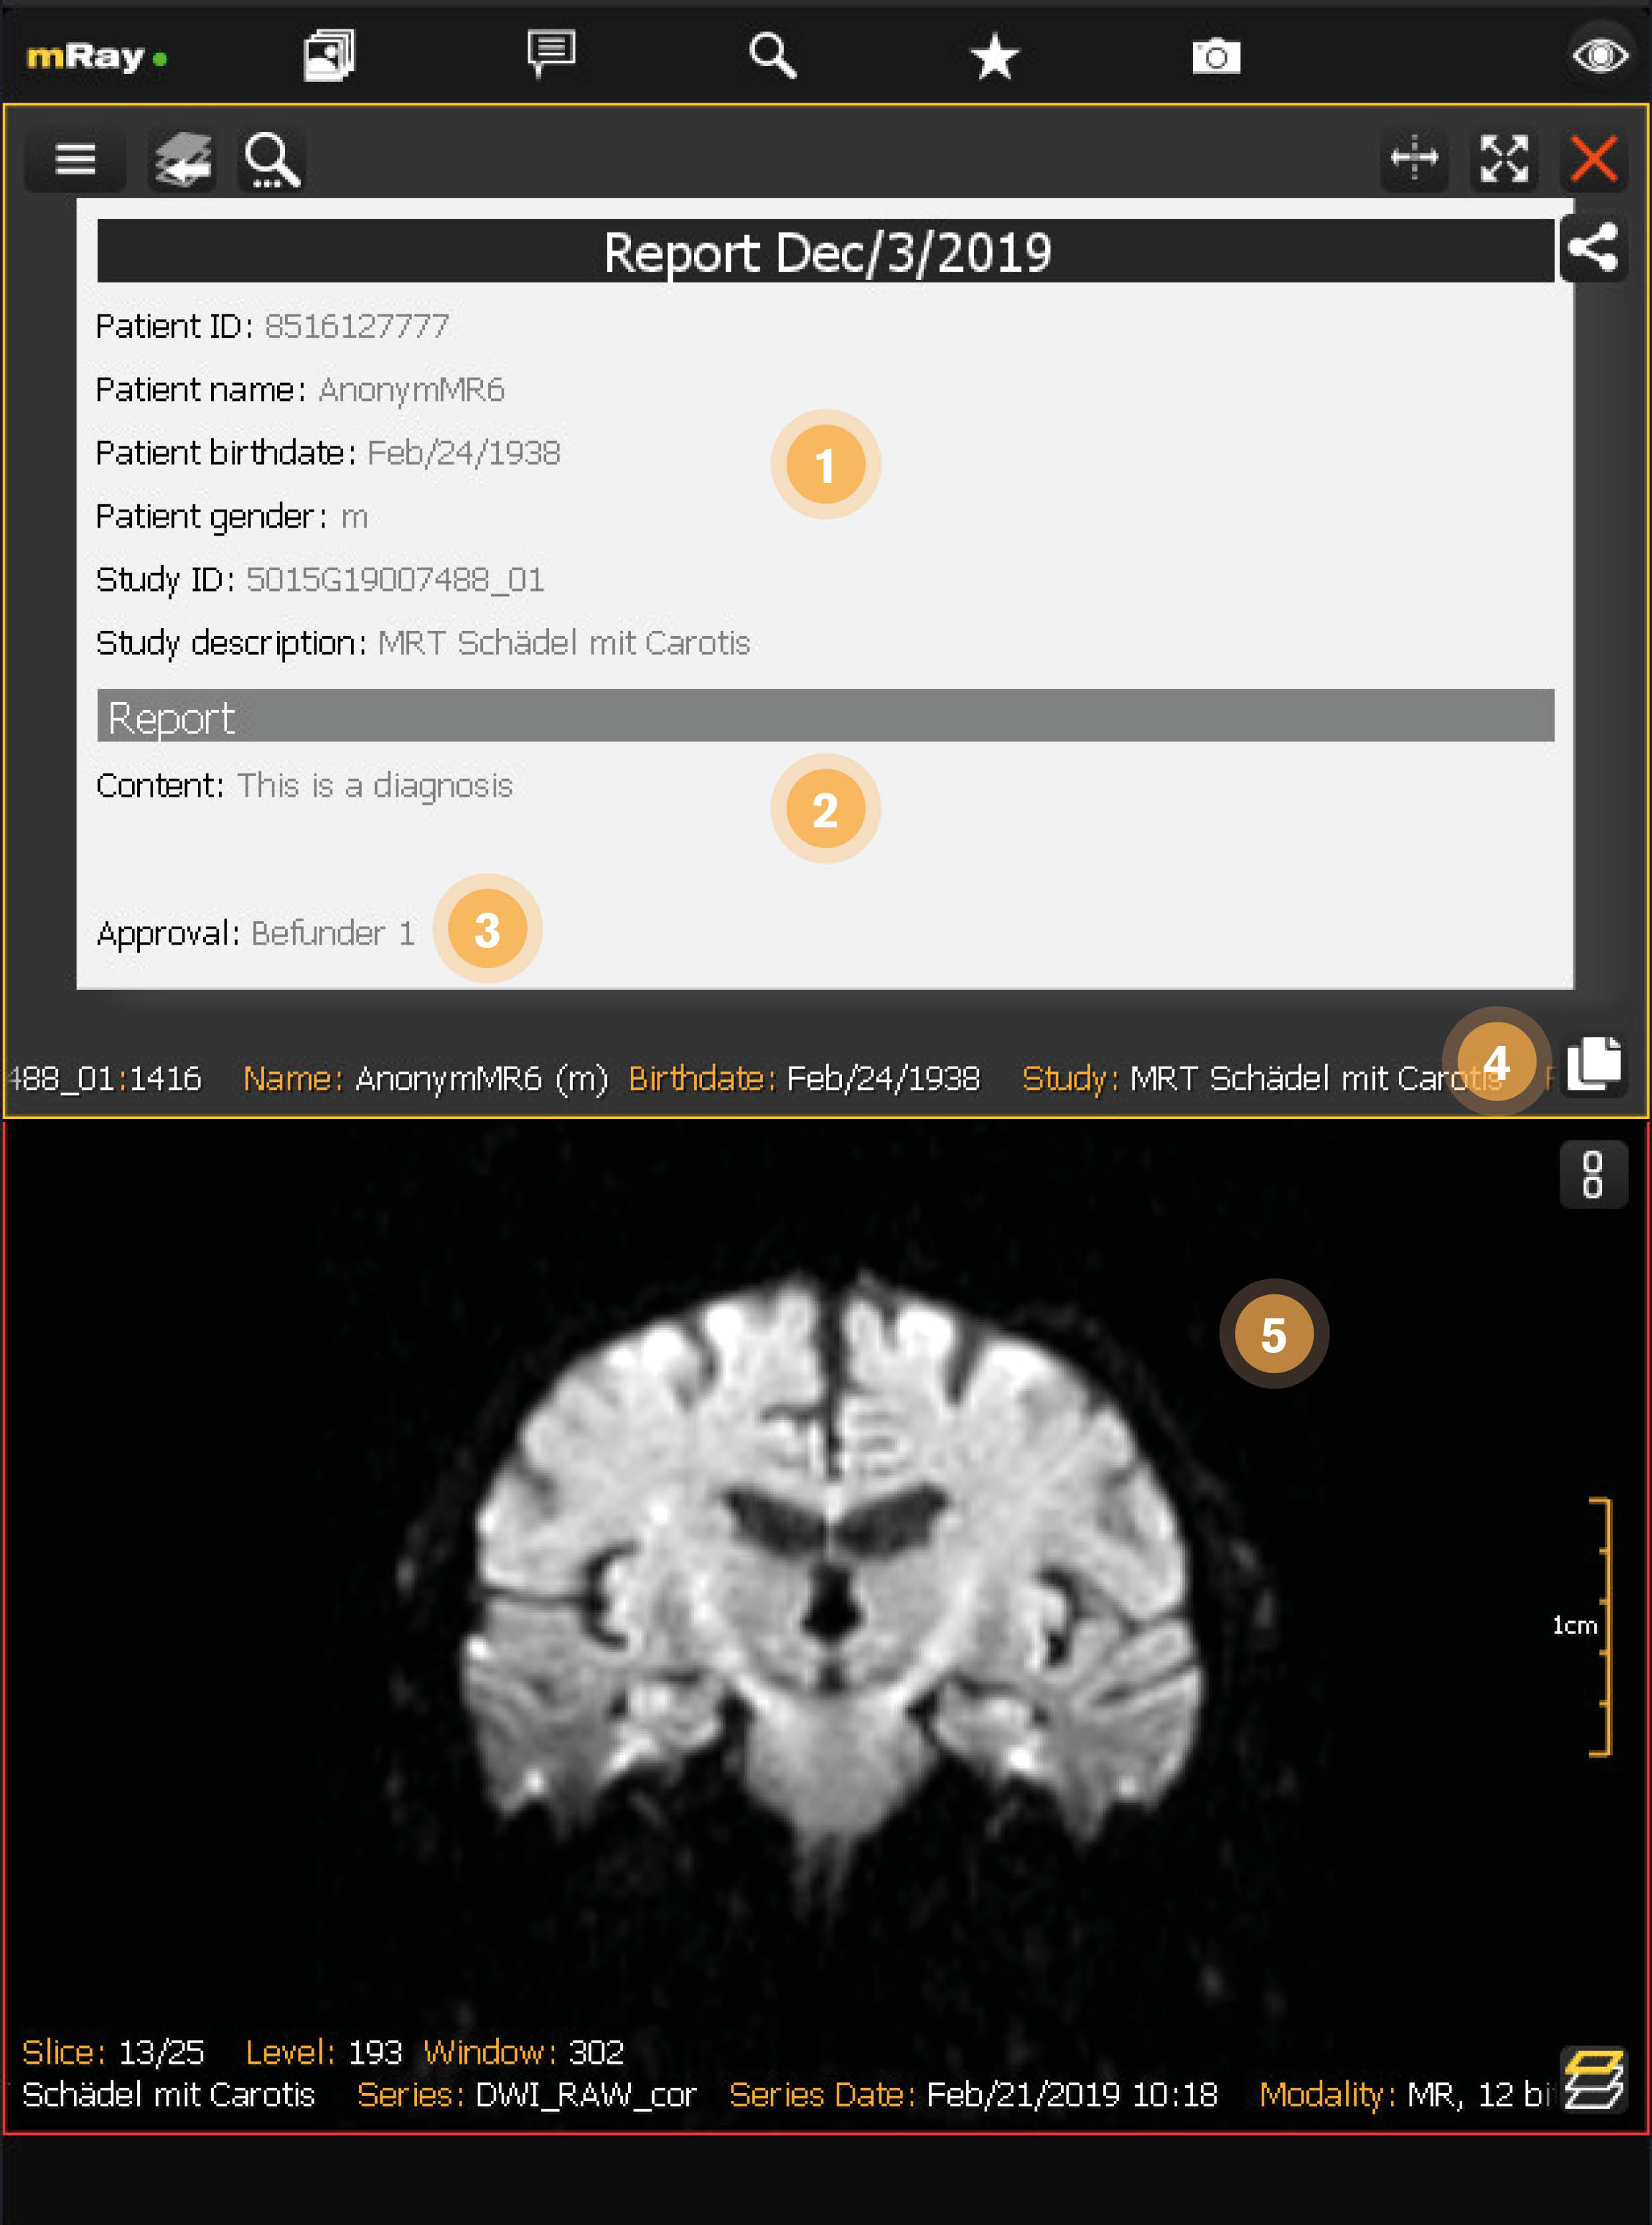

12.5. Structured report view

After the draft has been approved it’s not editable anymore and the draft flag is removed. See Final structured report

-

Report summary: A summary of the information in this report.

-

Report content: The text that has been added to this report.

-

Report approval: Displays the user who has approved the report.

-

Copy content: Puts the content of this report into your clipboard.

-

Associated study: Displays the study that is associated with this report.

|

You can automatically export approved reports into your PACS when your mRay Server has that feature. Please contact your mbits support for further information. |